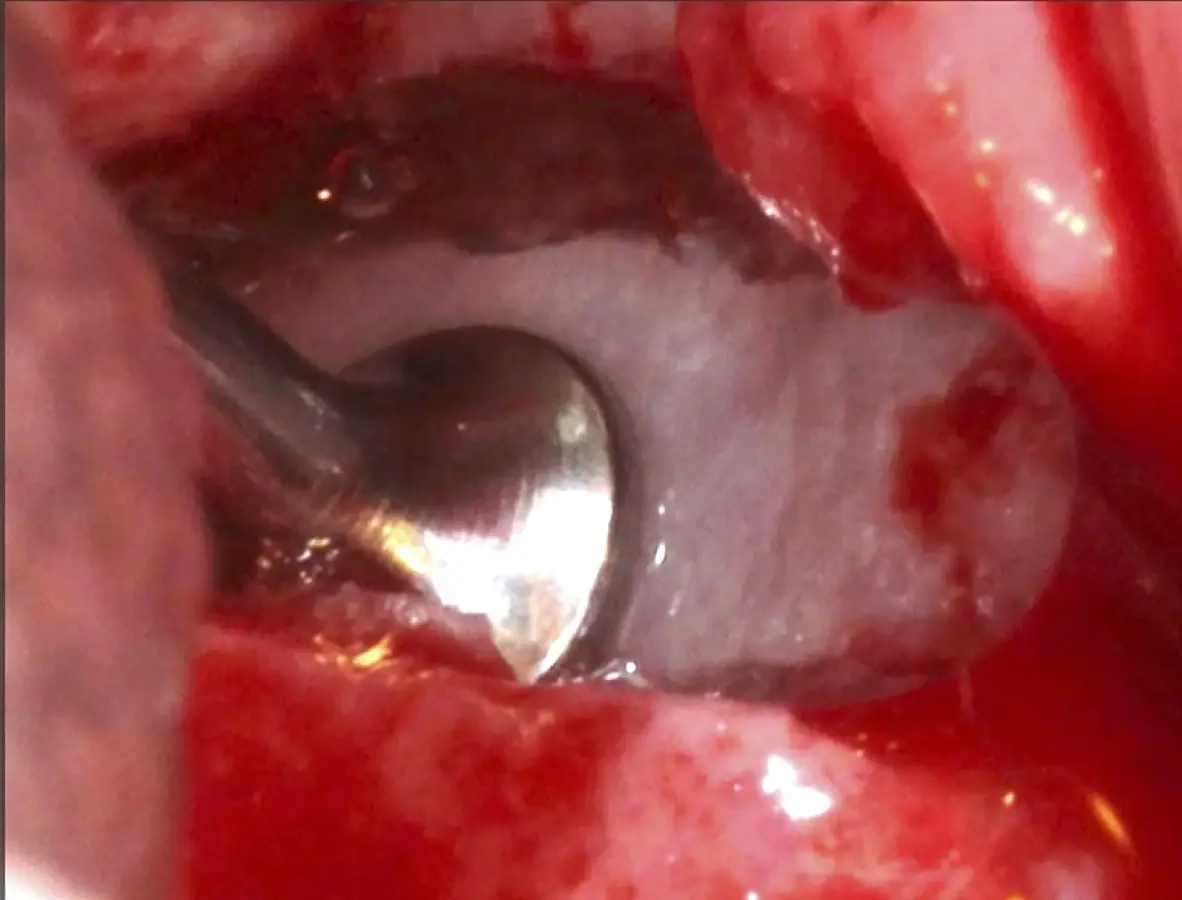

Se inicia la elevación de la membrana de Schneider con el inserto redondeado no cortante en forma de disco, empleando movimientos suaves. El levantamiento puede complementarse con elevadores convencionales, siguiendo la dirección mesiodistal. La fase de desprendimiento inicia con el piso y sigue hacia la pared mesial para terminar, y de ser necesario, hacia la pared posterior. Existen diversos insertos con angulaciones y longitudes para mayor accesibilidad16 (Figura 1).

Inserto de presión hidráulica iniciando el desprendimiento de la membrana de Schneider (a, b ).

Figura 7. Inserto de presión hidráulica iniciando el desprendimiento de la membrana de Schneider (a, b ).

Figura 17. Inicio del desprendimiento de la membrana de Schneider con el inserto de presión hidráulica.

Figura 25. Introducción del bloque óseo de la pared lateral dentro del seno maxilar: inicio del desprendimiento de la membrana con el inserto de presión hidráulica.